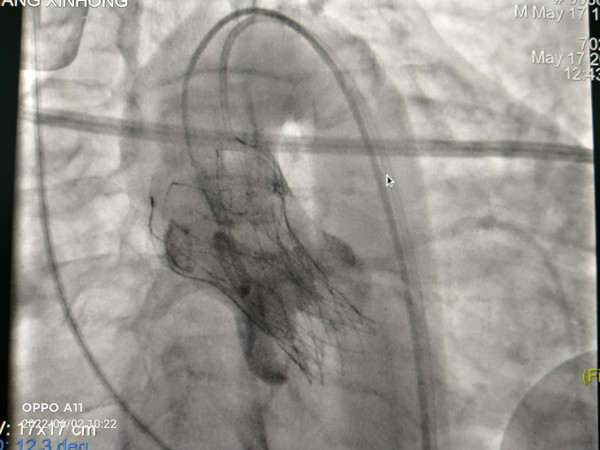

在我院心外科裴斐主任医师,麻醉科刘鹏斌主任医师、罗斌主治医师,超声科韩东刚副主任医师、金鑫主治医师,曹春晖护士长领导的护理团队等多学科协助下,韩振华主任、王新宏副主任医师、刘小军主治医师等先为患者行冠脉造影提示右冠近段95%狭窄(图1),先行PCI干预,右冠植入3.0x22mm支架1枚(图2)。后成功为患者植入TAV24mm VitaFlow瓣膜系统,DSA造影显示主动脉瓣位置良好,未见明显瓣周漏(图3),左右冠脉造影正常,术后即刻心脏超声示最大跨瓣流速129cm/s,最大跨瓣压差7mmHg(图4),顺利结束手术。